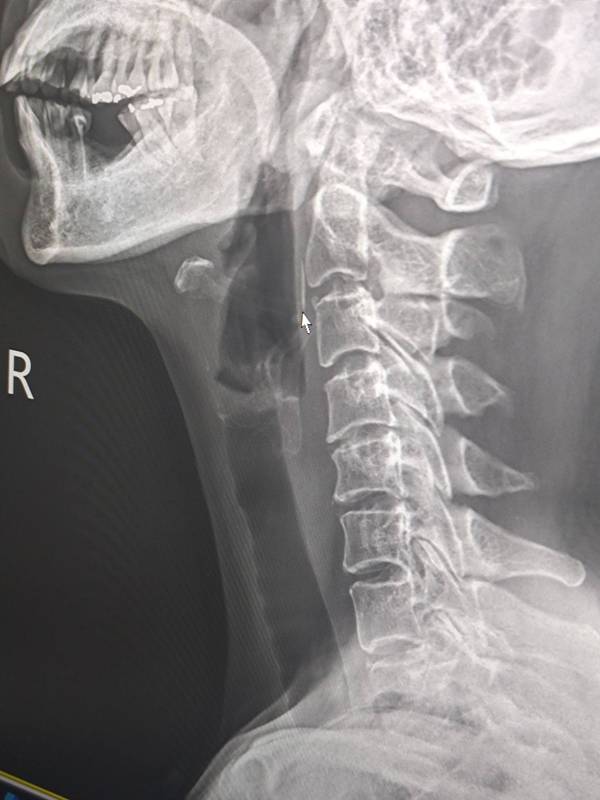

ภาพจาก เฟซบุ๊ก Rungravee Chaiwirattikul